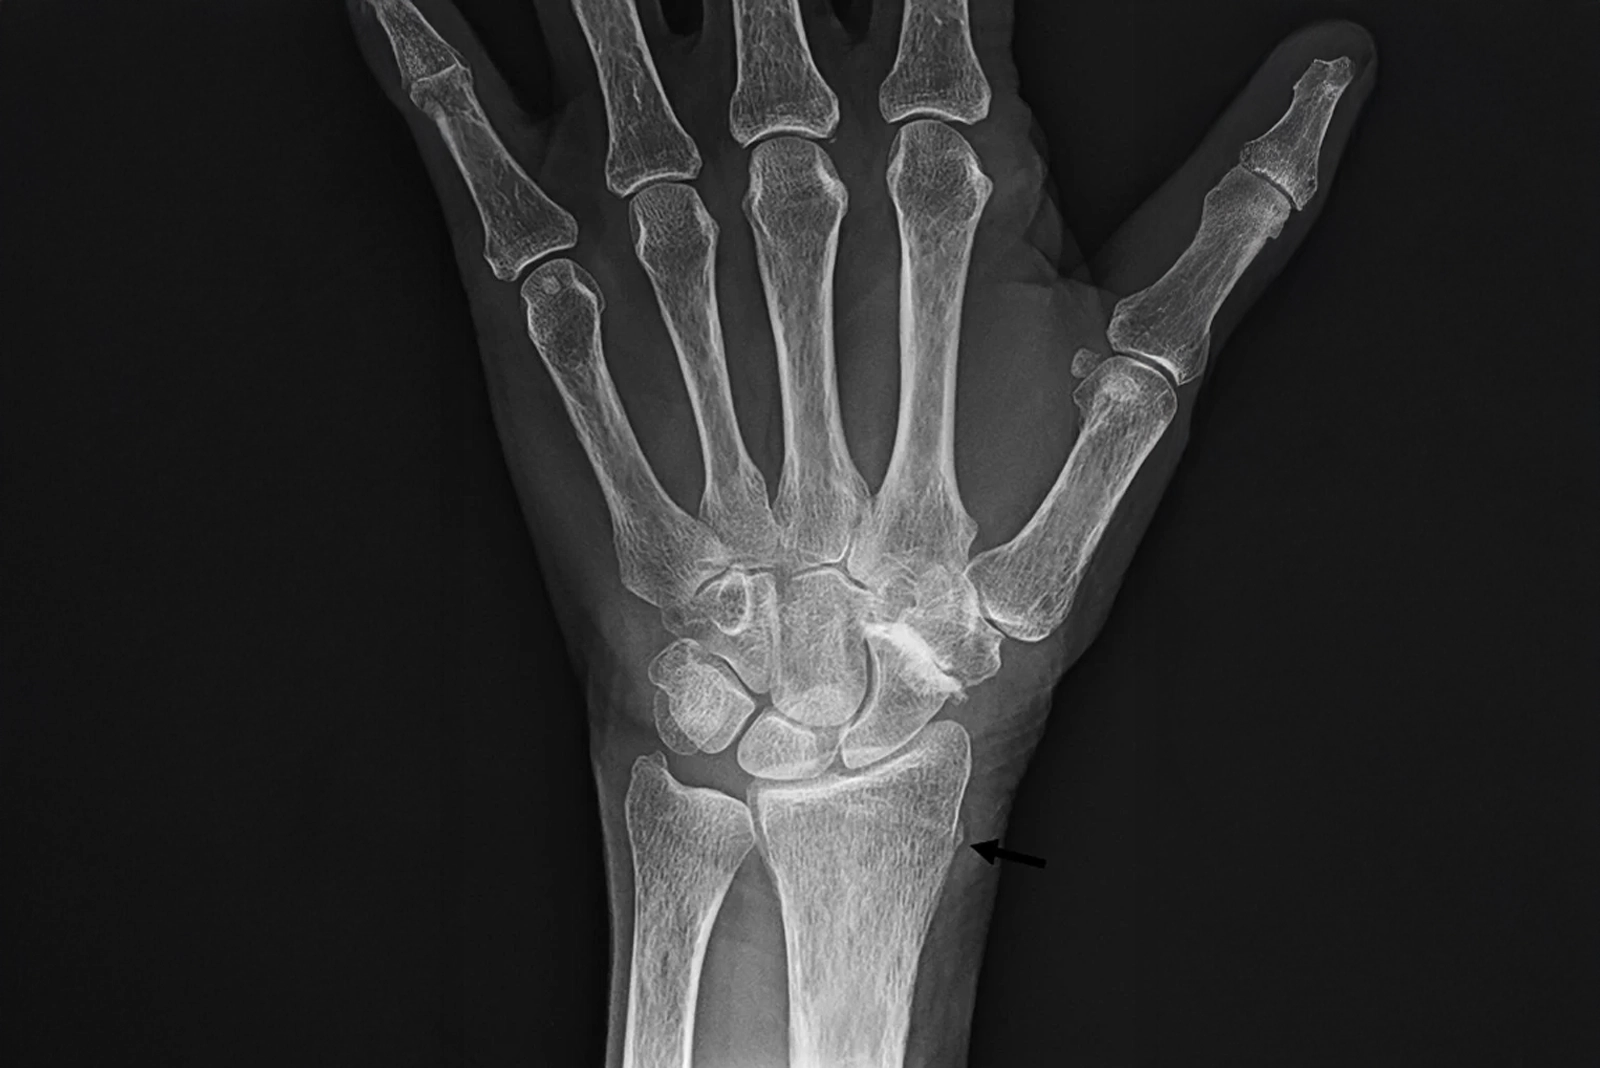

Diagnosis of Hand & Wrist